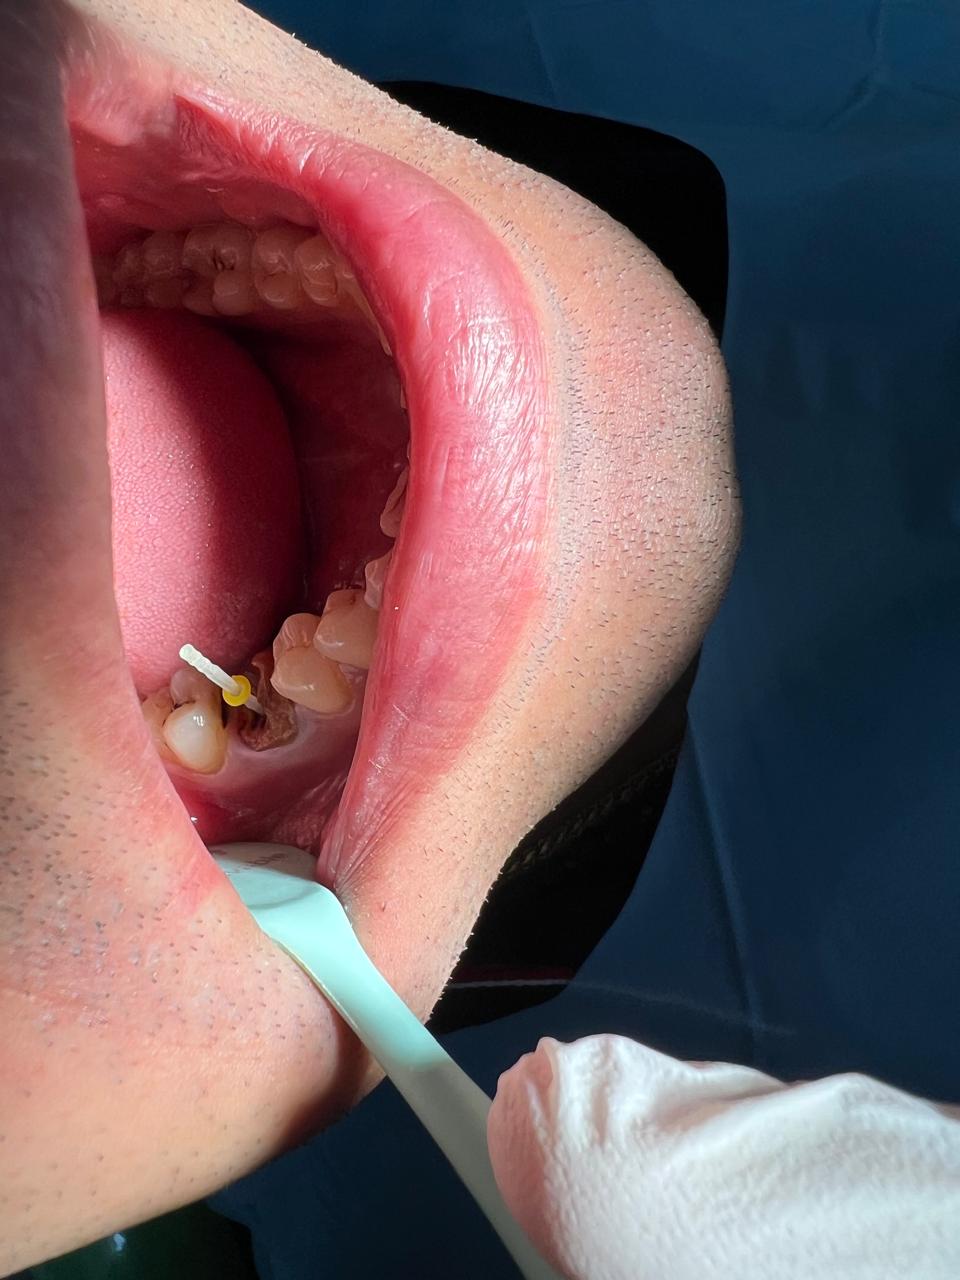

Clinical Findings

Upon examination, an intraoral sinus tract was observed adjacent to a previously root canal-treated tooth. The tract was non-tender but discharged pus on slight pressure. The crown appeared intact externally.